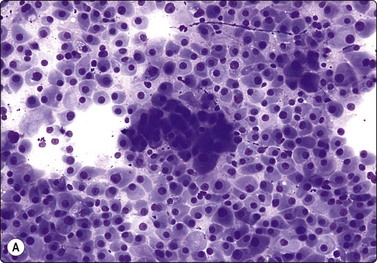

Nasopharyngeal carcinoma (NPC) (Figs 4.8, 4.9, and 5.59)44-47

image

Fig. 4.8 Nasopharyngeal carcinoma (squamous cell carcinoma, WHO type II)

Epithelial fragment of spindly and basaloid squamous epithelial cells with no evidence of keratinization (Pap, HP).

image image

Fig. 4.9 Nasopharyngeal carcinoma (undifferentiated, lymphoepithelial type, WHO type III)

Loose clusters of undifferentiated epithelial cells with vesicular nuclei, prominent nucleoli and pale fragile cytoplasm. Background of lymphocytes. (A, MGG, HP; B, H&E, HP).

Criteria for diagnosis (undifferentiated carcinoma nasopharyngeal type (UCNT)/WHO type III/lymphoepithelial carcinoma)

Undifferentiated malignant cells, single and in clusters,

Variable amount of pale, fragile cytoplasm,

Large vesicular nuclei with prominent central nucleoli,

Admixture with, and background of, lymphoid cells, often with prominent plasma cells,

Ancillary tests: neoplastic cells positive for cytokeratin, negative for lymphocyte markers. EBV-associated nuclear antigen.

Nasopharyngeal carcinoma (NPC) is a clinicopathologic entity different from other squamous cell carcinomata of the head and neck. It is distinguished by its particular histology, geographic distribution, relationship to Epstein-Barr virus, and the absence of an alcohol or tobacco etiological relationship. A proportion of NPCs show squamous differentiation and the cytological pattern of non-keratinizing squamous cell carcinoma (squamous cell carcinoma/WHO type II) (Fig. 4.8). Keratinized cells (WHO type I) are uncommonly found. The majority of NPC are poorly differentiated or undifferentiated. Cells from undifferentiated NPC (UCNT, WHO type III) form loose clusters with no specific microarchitectural pattern, and are usually mixed with lymphoid cells. In the ‘lymphoepitheliomatous’ type (Schmincke-Regaud) the cells tend to be less cohesive, resembling Hodgkin’s disease or large cell non-Hodgkin lymphoma. However, in NPC, the malignant cells are still clustered and have more abundant pale cytoplasm contrasting with the lymphoid cells in the background (Fig. 4.9). Plasma cells are frequently found among the lymphoid cells. Immunostaining for cytokeratin and a pan-lymphocyte marker is helpful. Epstein-Barr virus-associated nuclear antigen is demonstrable by anticomplement immunofluorescence in undifferentiated tumors. Other patterns of growth may occur and may cause diagnostic problems; for example, spindle cell forms may be difficult to recognize as carcinoma.

NPC frequently presents to the cytologist as a lymph node metastasis in the neck without a known primary. Cytological recognition is important since the primary is often clinically occult.